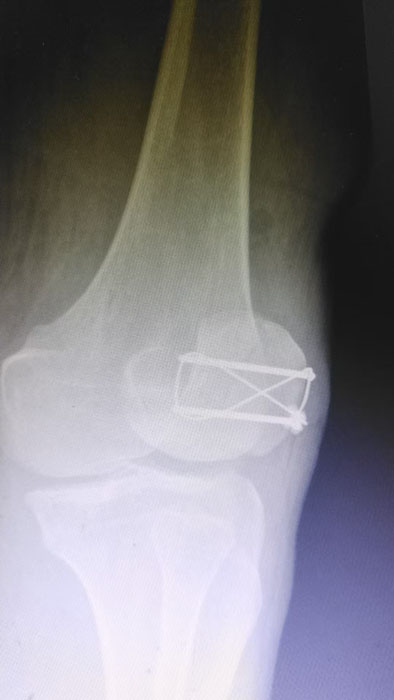

手术现场,徐三军主任凭借多年积累的临床经验和娴熟的手术技巧,精准完成骨折复位、钢板内固定、伤口缝合等一系列关键操作,动作规范流畅、精准高效,最大限度减少手术创伤。该院外科医护团队全程密切配合、协同发力,严格按照手术规范操作,全程严密监测患者心率、血压等生命体征,及时应对术中各类突发情况,全力保障手术安全。此次手术全程顺利,术中出血量少,患者生命体征始终平稳,术后患者顺利安返病房,为后续康复治疗奠定了坚实基础。

此次手术不仅是一次成功的临床救治实践,更是一堂生动鲜活的“实战教学课”。手术过程中,徐三军结合自身临床经验,同步向该院外科医护人员讲解髌骨骨折手术的操作要点、规范流程、风险防控技巧及术后康复核心要点,采取“手把手”带教、点对点指导的方式,耐心解答医护人员提出的疑问,帮助基层医护人员理清诊疗思路、提升操作能力。此次带教有效提升了卫生院外科团队在骨科手术及围手术期管理方面的专业水平,为基层医疗服务能力持续提升注入了强劲动力。